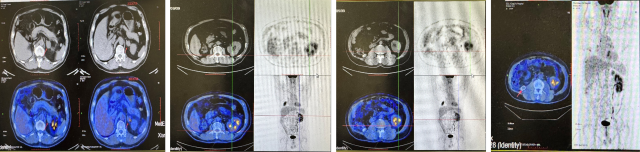

CT(2022.7):1. 右肺转移瘤切除术后改变;2. 左肾上腺结节,转移?3. 左肾多发结节,转移瘤?4. 腹膜后淋巴结肿大,转移可能;5. 左肾多发小囊肿。

PETCT(2022.10):1. 左侧肾上腺结节灶,糖代谢增高,转移瘤可能性大;2. 左肾多发结节状突起,糖代谢增高,考虑转移瘤,需结合增强 CT 综合判断;3. 右下肺切除术后,术区未见复发;4. 右侧胸壁局部增厚、糖代谢增高,术后改变?建议追踪。

CT(2023.7.17):1. 左肾上腺结节、左肾结节及肿块较前明显增大:转移?左肾 CA 并左肾内、肾上腺转移?2. 腹膜后淋巴结较前增大,转移可能;3. 余况基本同前。

CT(2023.12.6):1. 左肾上腺结节较前稍缩小、左肾结节及肿块较前稍缩小;2. 腹膜后淋巴结转移灶同前;3. 余况基本同前。